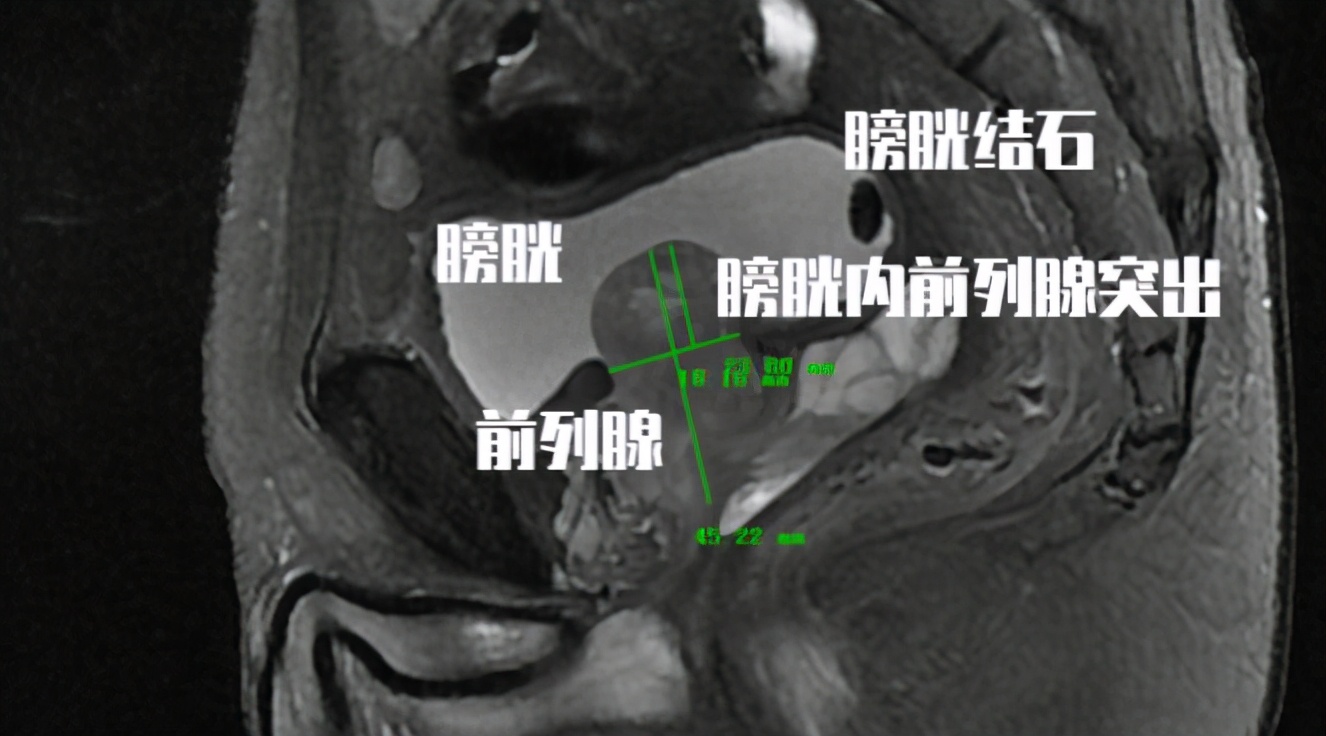

老王今年74岁, 3个月前自诉突发排尿困难,尿线变细来医院就诊 。在当地医院查CT提示 前列腺增生伴膀胱结石,最大膀胱结石体积1.8cm。 粗略估计了一下老王膀胱里的膀胱结石大概不下20颗。老王很奇怪, 为什么他有膀胱结石,而且有这么多结石,但是为什么自己什么感觉都没有呢?

答: 来自于第九版《外科学》教材对于膀胱结石临床症状的描述是: 排尿突然中断,疼痛放射至远端尿道及阴茎头部,伴排尿困难和膀胱刺激症状,可同时伴发血尿和感染。 但这个时候我们来回顾一下前列腺增生的临床症状我们不难发现, 膀胱结石的症状和前列腺增生的症状可以说是一一对应的。 那这个时候对于很多前列腺增生的患者, 如果不做彩超检查,有可能膀胱结石就被漏诊了!

答: 膀胱结石分为 原发性和继发性 ,一般前列腺增生患者出现的膀胱结石都是 因为前列腺增生所导致的继发性膀胱结石。 从病因和先后顺序来看,好像都应该是先将前列腺增生所解除。 目前临床上对于前列腺增生合并膀胱结石的患者,一般都可以同期将两个问题同时解决 ,但是出于患者身体耐受麻醉的程度和现阶段医保对于前列腺增生所采用的单病种政策,很多患者都需要接受分次手术。那么这两个问题应该哪个先处理?